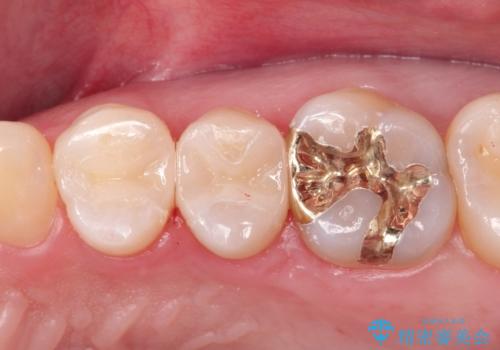

金属の詰め物を外してセラミックインレーに

- 矯正終了後に見た目をきれいにしたい希望があり、金属の詰め物を外してセラミックにて修復処置をしました。

セラミックインレーは天然の歯に近い透明感や色調を再現することが可能です。治療では自然な見た目になるまで追及しますので患者さんには非常に満足していただけました。